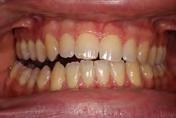

The patient finished with Class I occlusion, ideal overbite and overjet. The arches are co-

Figure 5. Final records.

ordinated, lateral open bite closed and occlusal cants leveled. From the frontal cephalometric tracings, maxillary width increased from 58 mm to 69 mm. From the lateral cephalometric tracing, the incisor angulations remained unchanged. The final report from the myofunctional therapist indicated the patient eliminated the bilateral posterior tongue-thrust swallowing pattern with saliva, liquid and solid swallows. Correct swallowing mechanics were demonstrated while sipping/gulping liquids from a cup. His day and nighttime tongue-resting postures were reported to be on his incisive papilla, with lateral margins lightly suctioned into the upper arch. Lips were closed and competent diurnally and nocturnally.

Most recent records are two years after removal of the orthodontic appliances, demonstrating the stability of the results (Figure 7).